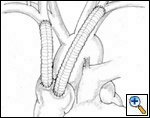

SVC replacement: replacement of the whole body of the SVC is the most frequent type of reconstruction (Figure 8). In patients with lung cancer, it is usually associated with right upper lobectomy or pneumonectomy; however, SVC reconstruction may be required during carinal pneumonectomy, sleeve lobectomy (Figure 9), and reconstructive procedures of the pulmonary artery[5]; the latter two should always be attempted if they help to avoid pneumonectomy. SVC replacement requires a tumor–free confluence of both brachiocephalic veins. The reconstruction is usually performed using a straight non-ringed PTFE graft (18 – 20 mm). An autologous or bovine pericardial tube could also be used (Figure 10). After proximal and distal clamping, the SVC is excised. The proximal anastomosis is performed first, using a 5-0 polypropylene suture, starting from the posterior aspect of the prosthesis or the tube of pericardium. The distal anastomosis is subsequently performed with the same technique. Before tying the distal suture line, the proximal clamp is gently released and deaeration is performed; afterwards, the distal clamp is released and knots are tied. After complete filling of the graft by blood, there should be no tension of the suture lines or torsion or kinking.

Sometimes it may be indicated to replace only one brachiocephalic vein (either the right or left, according to local invasion). A ringed PTFE graft should be used (Figure 11, 12), especially for the left vessel and the distal anastomosis should be performed on the inferior stump of the SVC or on the right atrium. Use of the auricle should be avoided because of the presence of the pectinate muscles. In this situation, the prosthesis may be too long after closure of median sternotomy and could kink easily. Also postoperative mediastinal fibrosis (especially if radiotherapy is administered) could contribute to graft compression. Simultaneous revascularization of both brachiocephalic veins (Figure 13) is rarely required since there are enough anastomotic venous communications in the neck. Revascularization of both systems is indicated in case of previous neck surgery (laryngeal or thyroid surgery for cancer); a separate distal anastomosis of the two grafts is preferred to avoid thrombosis of the accessory left limb of a Y graft, starting at the level of the graft–to–graft anastomosis.